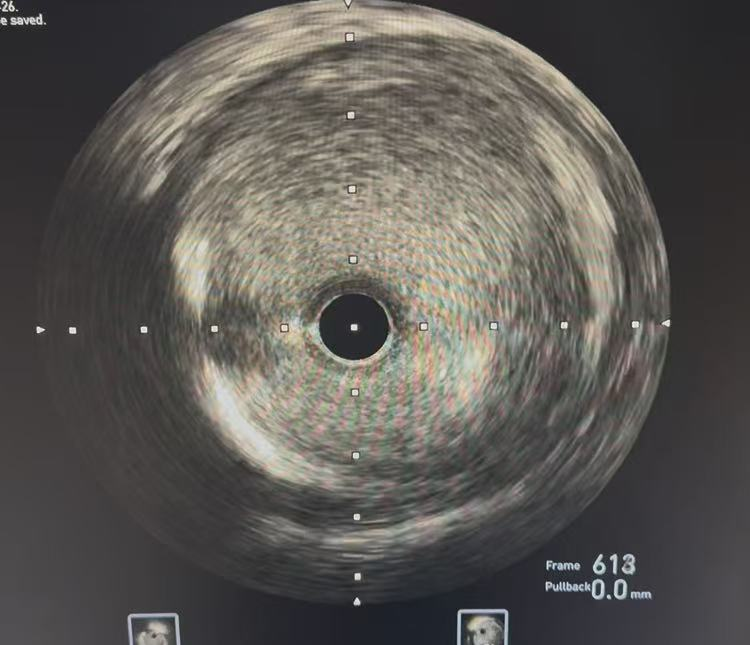

很快,姜先生被医护人员推入了急诊介入室。心血管科副主任医师张竹华、主治医师张振民迅速为姜先生完善了冠状动脉造影检查。结果提示姜先生左前降支近段管腔异常粗大,并伴有自发夹层形成;为充分评估血管情况,通过冠状动脉血管内超声(IVUS)检查,确认了姜先生本次心肌梗死就是因为冠脉自发夹层导致的,且左前降支近段异常粗大,最大直径已超过8mm。

IVUS验证夹层存在,管腔最大直径超过8mm